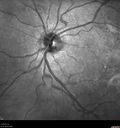

FUNDUS PHOTOGRAPHY - INFRA RED: The image shows very little change, it is nearly normal.